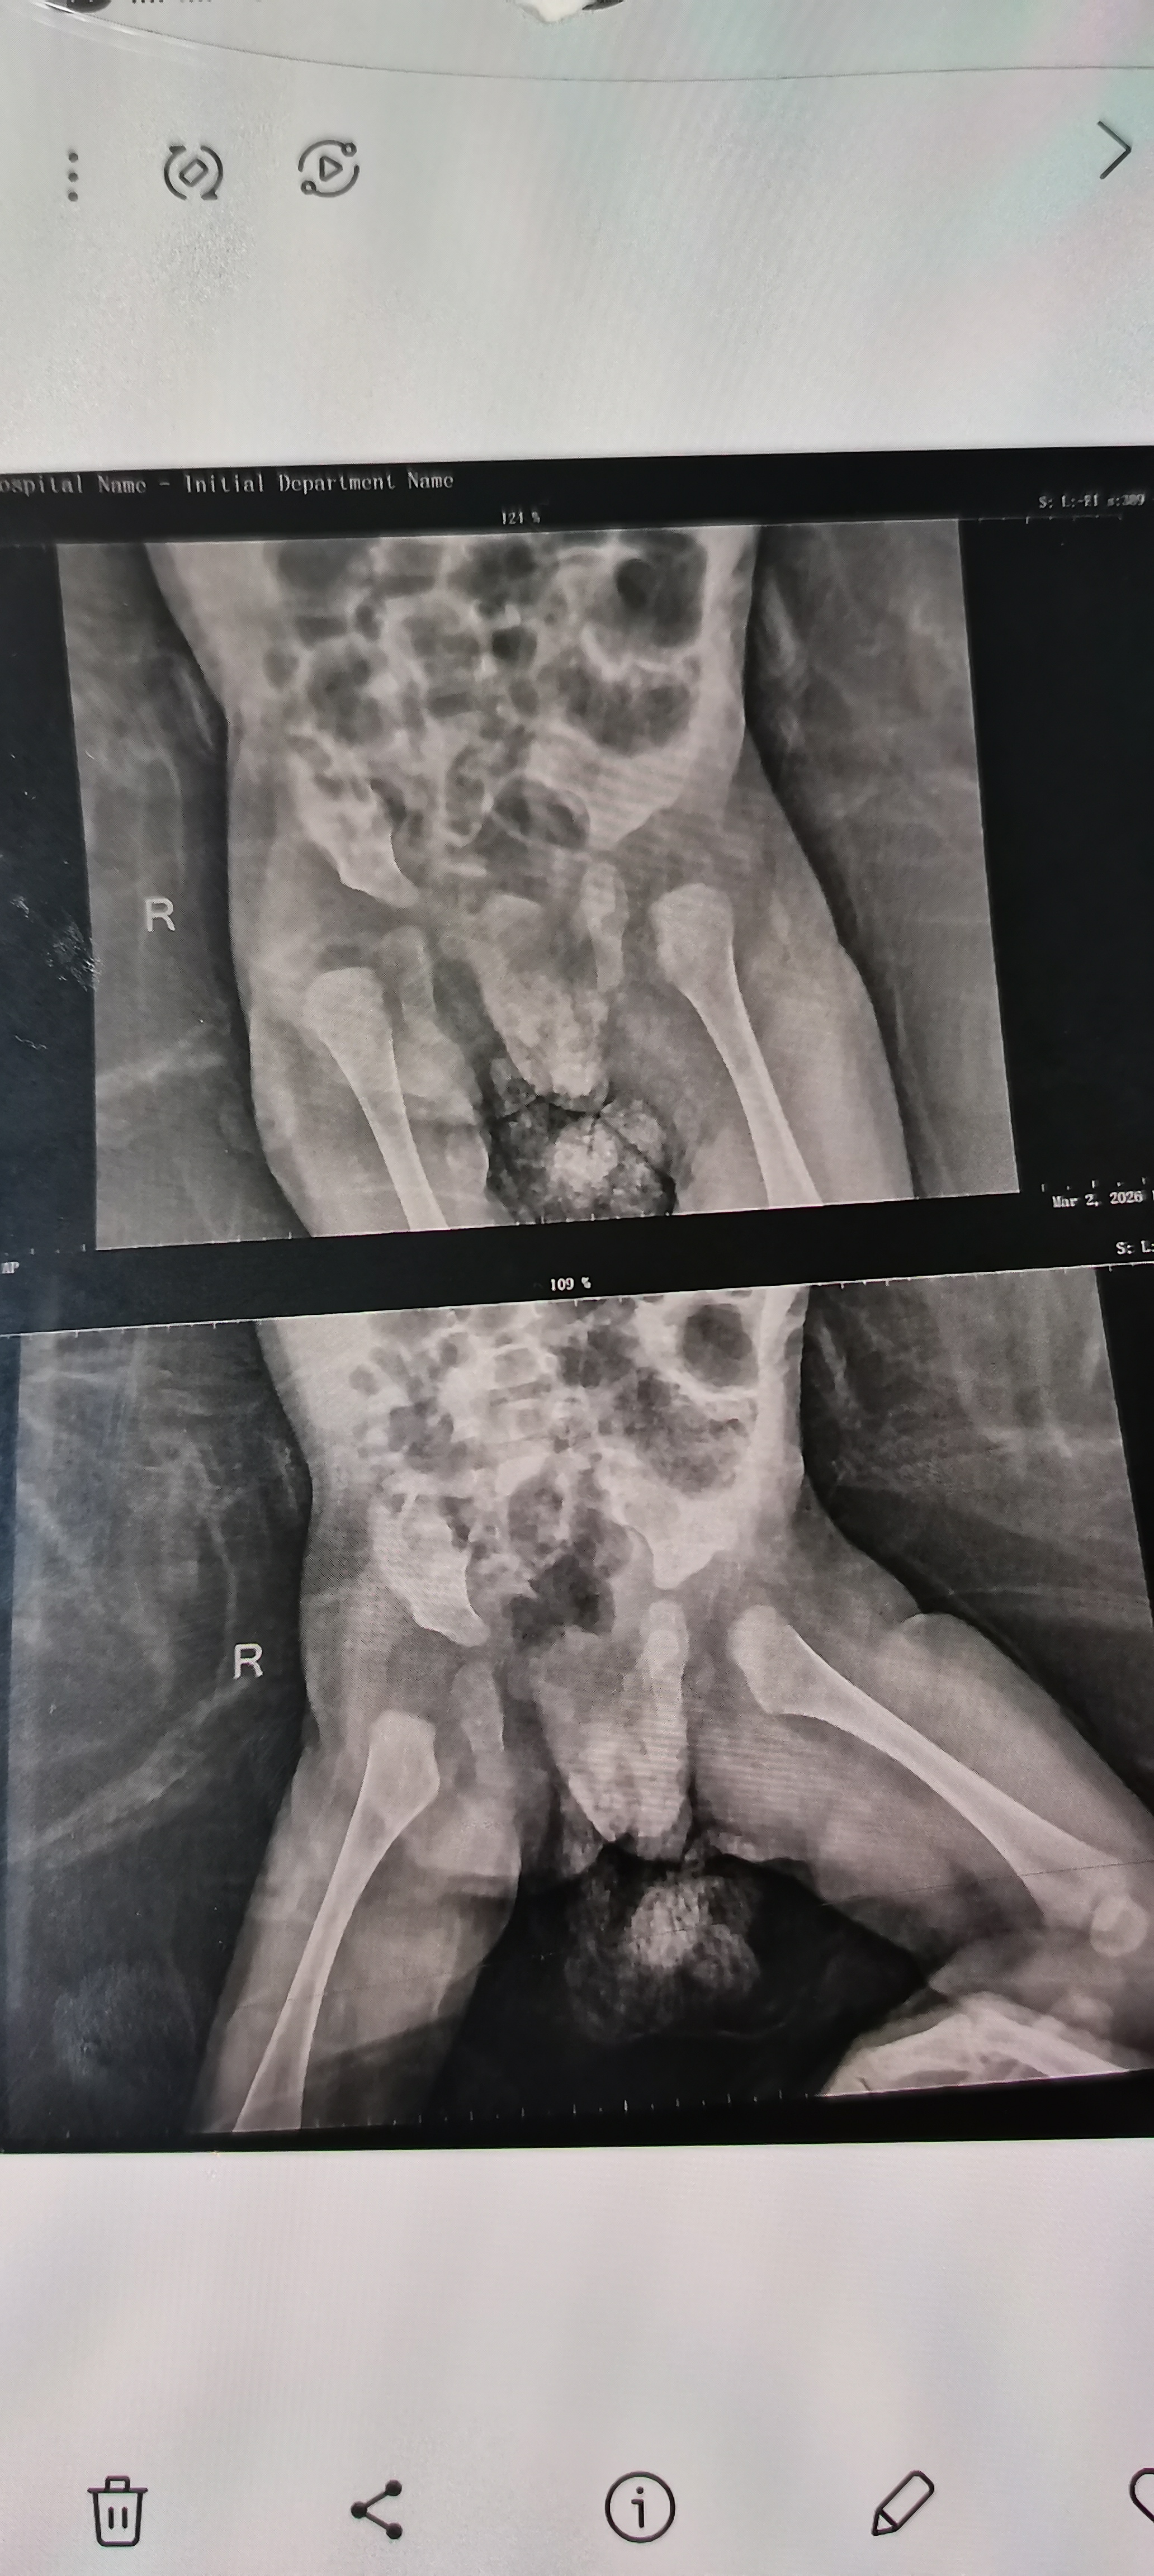

دى اشعة على مفصل الحوض، هل يوجد خلع بالورك، واى رجل اليمنى ام اليسرى، ودرجة الخلع؟ والحل الطبى

من الوراد يكون ف خلع بالجهة اليمني لكن الفحص ضروري جدا وايضا اجراء سونار ع عظام الحوض والعمر المثالي له قبل ٤ شهور فالرجاء مراجعة طبيب عظام اطفال او طبيب اطفال ف اقرب وقت 0 2026-03-13T21:46:08+00:00 2026-03-13T21:46:08+00:00

من الوراد يكون ف خلع بالجهة اليمني لكن الفحص ضروري جدا وايضا اجراء سونار ع عظام الحوض والعمر المثالي له قبل ٤ شهور فالرجاء مراجعة طبيب عظام اطفال او طبيب اطفال ف اقرب وقت